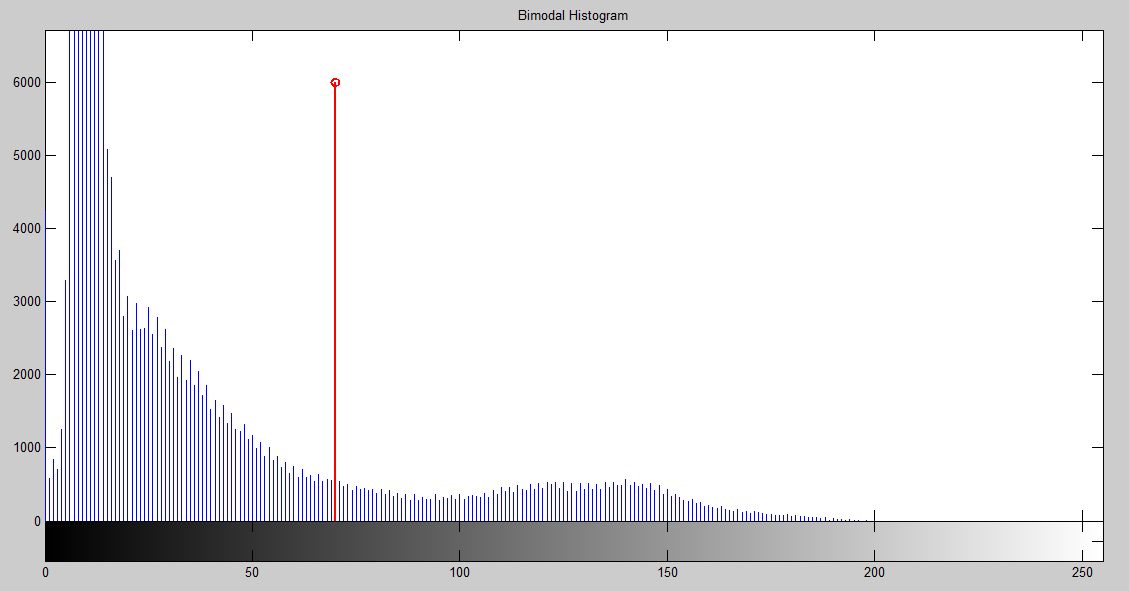

2.4.2 Thresholding (Otsu’s method)

The fat percentage in the ROI mainly depends on the choice of threshold value. To provide an initial reference to the user, the global image threshold calculated by Otsu’s method is included in the GUI. Basically, Otsu’s thresholding method considers that an image comprises of two classes of pixel intensity levels which can fall into a bi-modal histogram and an optimal threshold separating the two classes of pixels can be obtained such that their combined spread or intra-class variance is minimal. A bimodal histogram plot for an input image (Figure 2) is shown in Figure 5 with the threshold level 70, calculated using Otsu’s method. The whole input image was used to build the bimodal histogram.